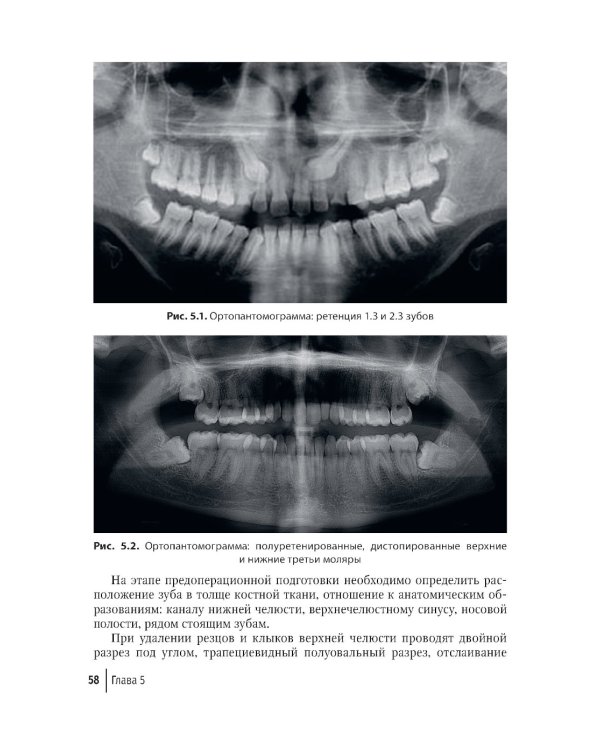

В руководстве представлены основные современные группы остеопластических материалов, применяемых в хирургии полости рта, описаны их характеристики и свойства. Приведены клинические примеры применения остеопластических материалов при альвеолосохраняющих методах удаления зубов с целью сохранения объема костной ткани, в реконструктивной хирургической стоматологии при удалении ретенированных зубов, операциях цистэктомии для заполнения костных полостей. Продемонстрирована значимость применения остеопластических материалов на этапах дентальной имплантации, при проведении субантральной аугментации, аугментации костного гребня при проведении операции для увеличения объема костной ткани. Даны примеры использования остеопластических материалов и мембран при проведении направленной костной регенерации при лечении заболеваний пародонта, а также при лечении осложнений дентальной имплантации. Издание рассчитано на практикующих врачей - стоматологов-хирургов, ординаторов, аспирантов, а также студентов высших медицинских учебных заведений.